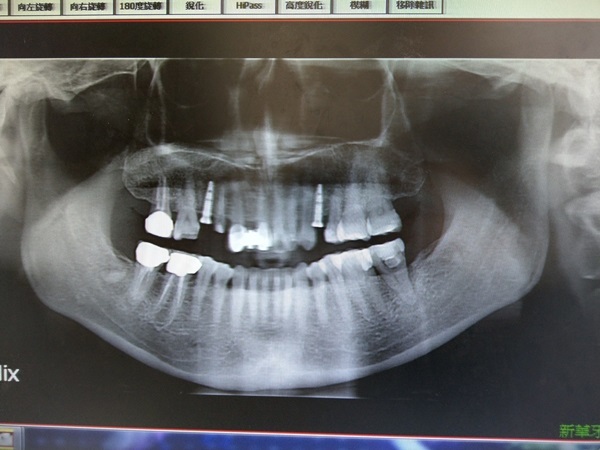

進到診間見到林醫師後,首先大概說明自己牙齒為何從過去的健康又整齊,開始出現現在讓我感到不安的情況,親切且態度溫和的林醫師先替我做了牙齒現階段情況的評估,並指出過去歷經車禍後,的確使周遭牙齒有鬆動現象,不過可能之前有先治療部分蛀牙,所以牙齒狀況還算良好,雖然最後他仍指出有數顆潛在性風險的候補存在,且說明原本鬆動的牙床會使蛀牙情況惡化速度加快,須趕快將該顆斷牙殘根拔除,進行人工植牙。

林醫師提到,由於我平常有抽菸盒吃檳榔的習慣缺牙齒槽骨質密度較低,不適合癒合速度較快、手術過程簡單,近年來十分風行的「微創植牙」,需進行一般的人工植牙手術。

他繼續解釋適合微創植牙患者所需具備條件,除了牙齒骨質密度需較高,缺牙狀況也不宜太過嚴重,而長期留住殘根在牙床內的我的斷牙,處理起來會較不容易,畢竟已經有部分牙肉將其包覆,指出再拖延下去,不只會影響到其他顆牙齒,殘根病變的風險也相對增高,接著則由護士小姐帶領我,進行植牙手術更細部的內容說明。

所以即使現階段醫師評估我的口腔狀況並不差,但仍須考量到未來的其他變數,做長期性的追蹤觀察。